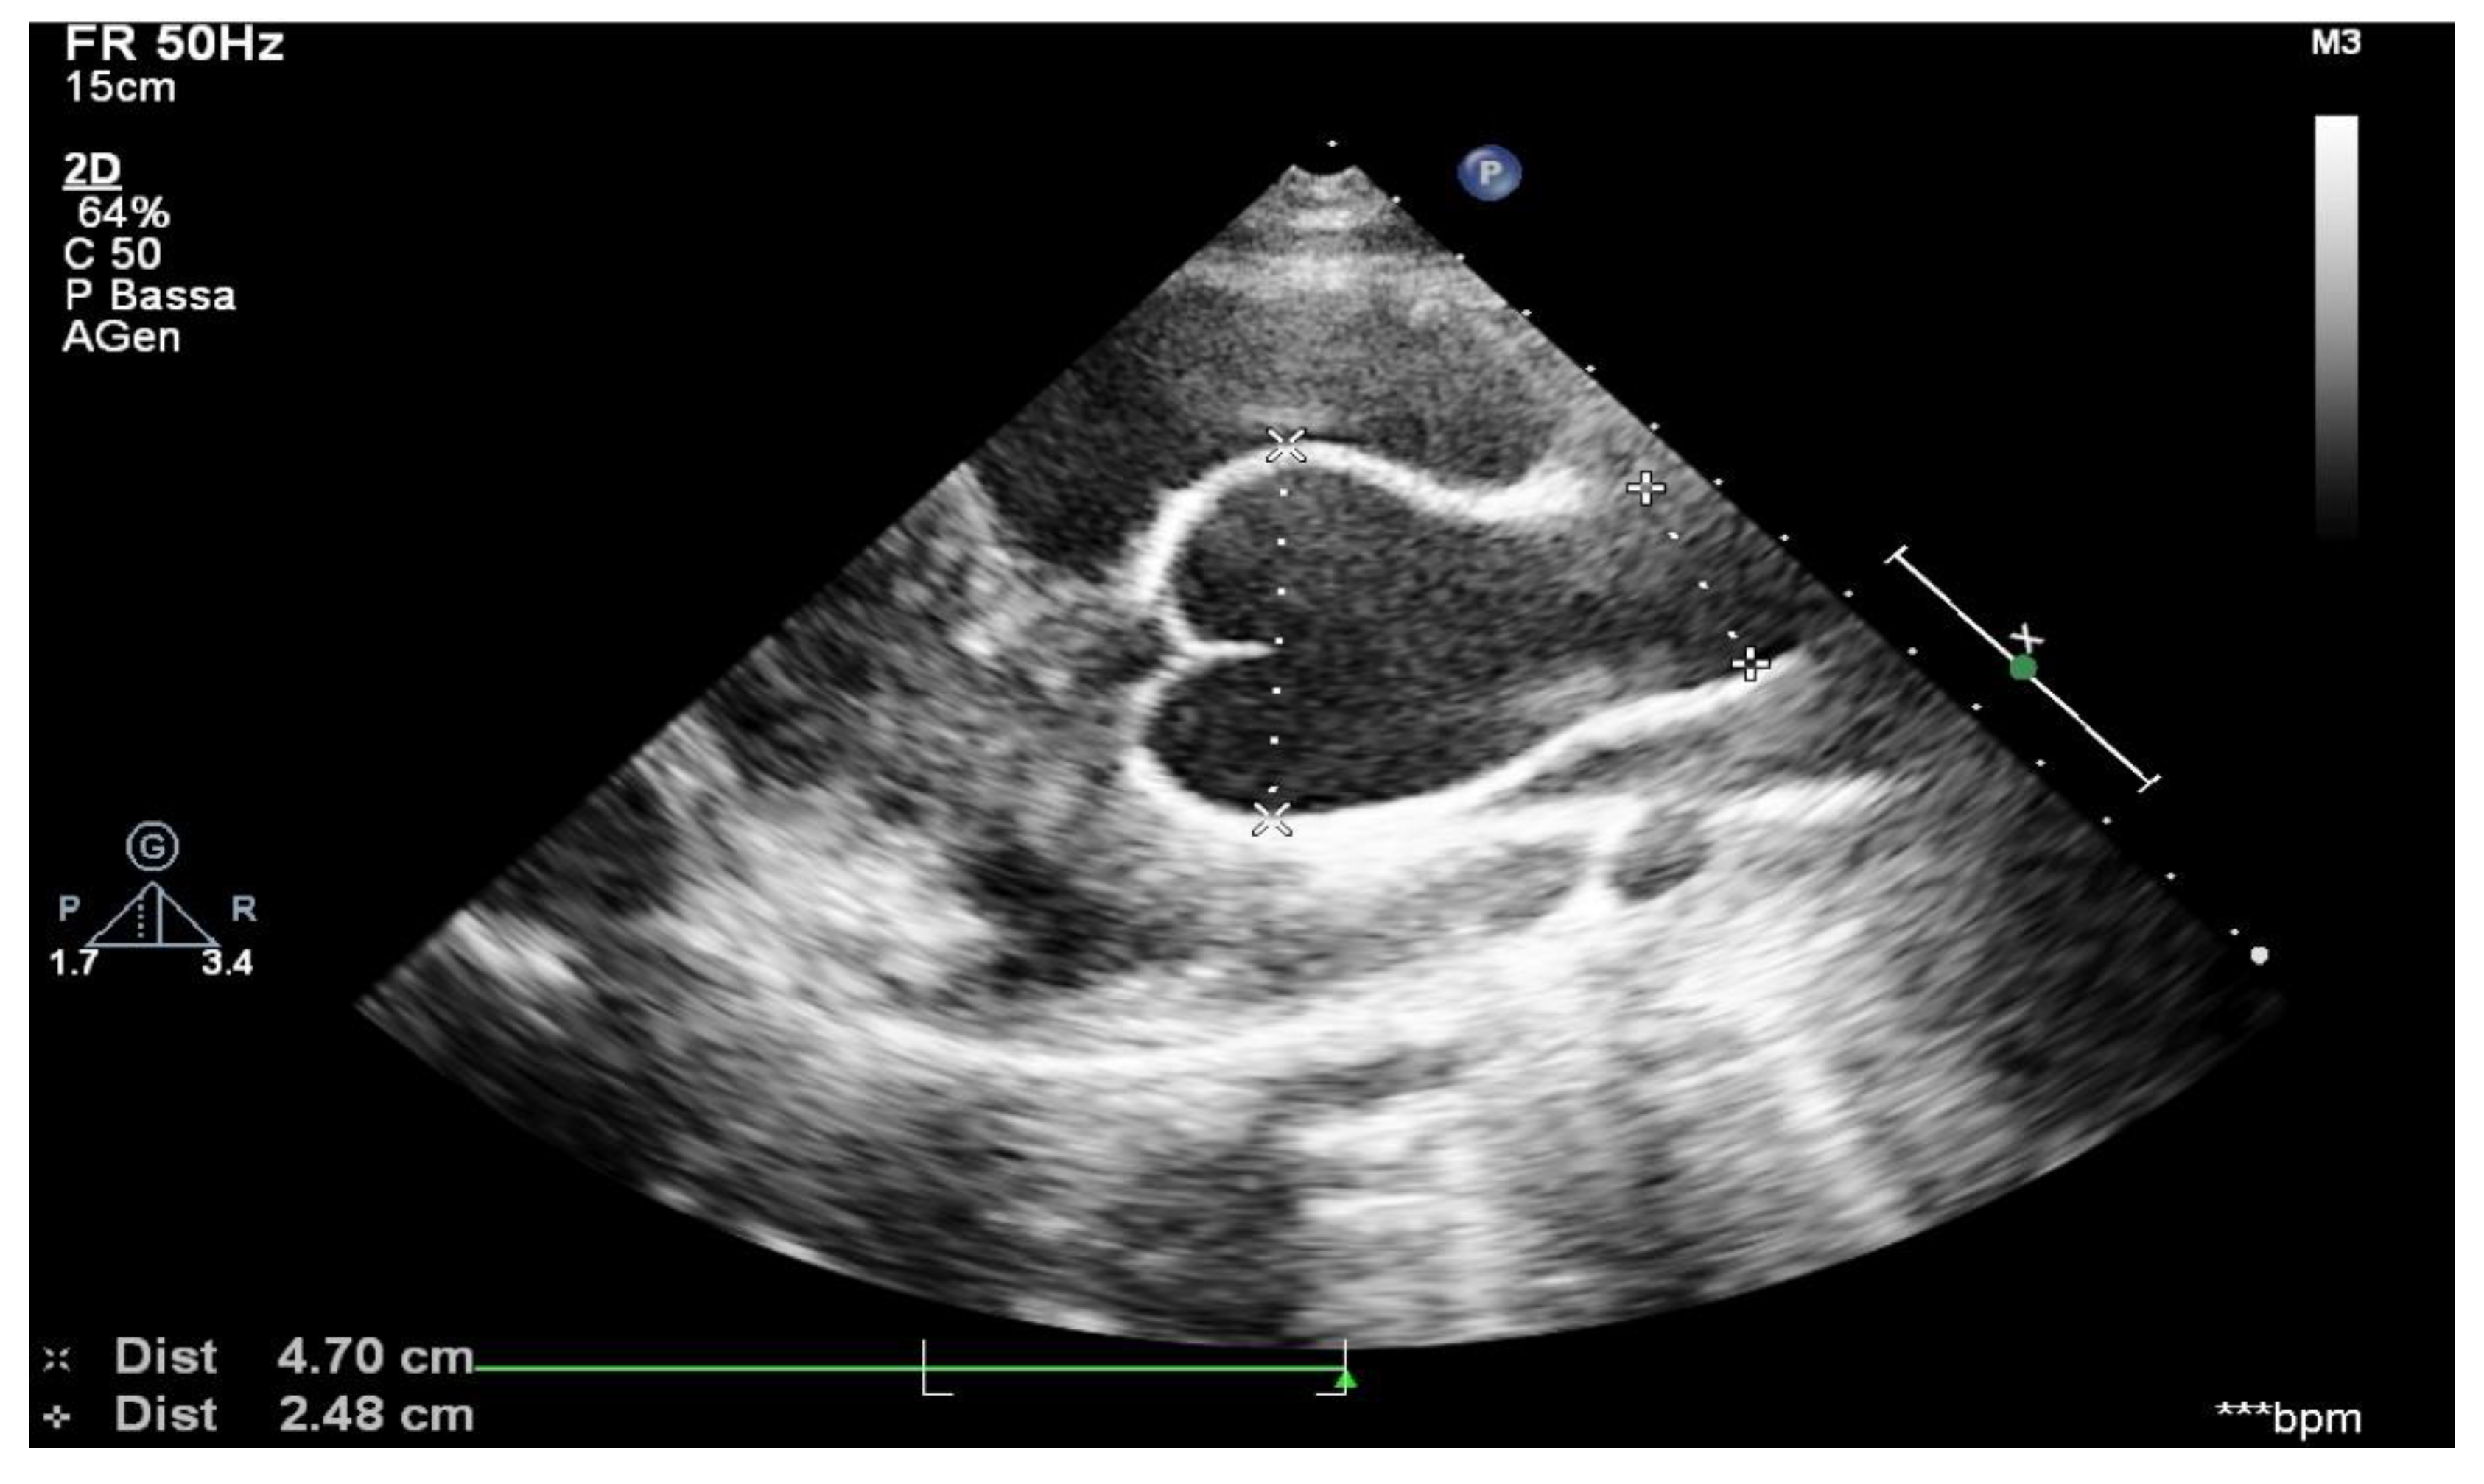

2.3. Echocardiographic Measurements

Aortic root measurements were obtained from transthoracic echocardiograms using American Society of Echocardiography recommendations [19]. The method was similar to that used by Gautier et al., and it followed the published recommendations [20]. Aortic root diameters were measured at five levels on a parasternal long-axis view: aortic annulus; Valsalva sinus; aortic bulb; sinotubular junction; and ascending aorta. The aortic annulus was measured in systole, whereas other aortic root diameters were measured in diastole. Aortic root measurements were taken from leading edge to leading edge, parallel to the plane of the aortic valve and perpendicular to the axis of the blood flow (Figure 1). Aortic root diameter Z-scores were calculated using Gautier’s formula. Z-scores are a means of expressing the deviation of a given measurement from the size-specific population mean. Aortic root dilation was defined as any aortic root measurement Z-score ≥ 2 at the Valsalva sinus level or at the sinotubular junction or at the ascending aorta level. The growth speed of aortic diameters was defined as the ratio between the difference of measured aortic diameters and the delay, in years, between two examinations. As a result of the natural growth of the aortic root in children, a threshold of maximum growth speed above the 90th percentile (5 mm per year) was set as being clinically relevant. The difference between the first and last Valsalva sinus Z-scores available during follow-up was calculated and divided by the delay between the two measurements to obtain the Valsalva sinus Z-score evolution speed during the follow-up period [21].

Figure 1. Aortic arch from suprasternal view.